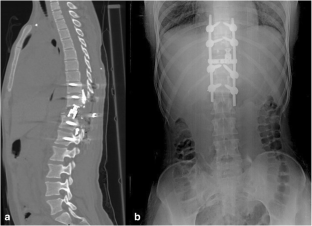

We report a 15-year-old female patient with thoracic giant cell tumor who underwent percutaneous vertebroplasty and had cement extravasation into the spinal canal. Because of the deterioration of the patient’s neurological condition, total enbloc spondylectomy and cement excision were performed. She underwent instrumentation and fusion procedures in order to prevent spinal instability.

Fig. 2